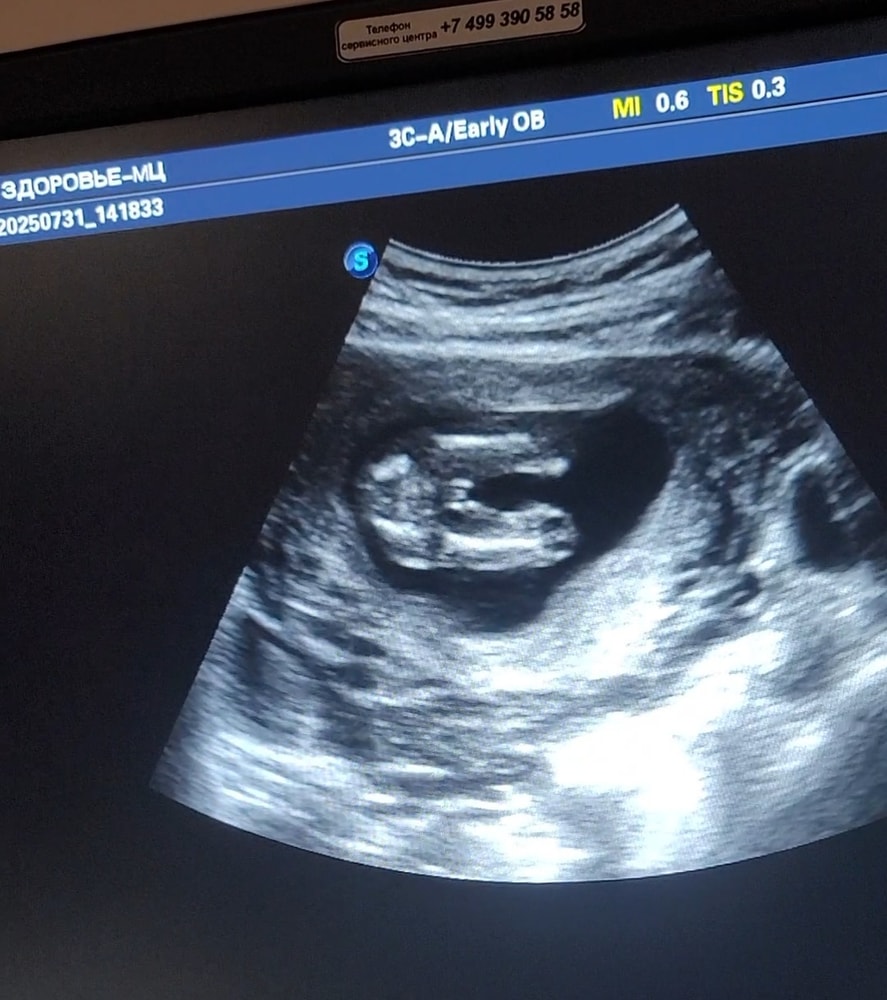

16-17 недель узи не могу понять мальчик или девочка

Была на узи в платном .Чисто на отвали посмотрели и дали конверт на руки .Снимок тоже не разборчив .Может вы увидите по снимке.Мальчик или девочка?

По моему, мошонка это. А пенис наверх смотрит, наверное. Но это я так вижу.

Жужу, да ну, явно же видно "кофейное зернышко". А вот на вашем снимке вижу прям мошонку)

Просто это может быть мошонка, а пенис вверх смотреть. У моей прям хорошо видно было, что половые губы и клитор,но и узи было в 20 нед., а тут я сразу подумала - мошонка...

Ирина, у меня просто после двух пацанов ,даже не знаю .Не могу увидеть писюн .УЗИ было на 16-17 неделе беременности 😅

Жужу, ну тут и не виден он. Или это мошонка или очень большие выпуклые губы. Ждите другое узи)

Жужу, вот такой листок дали .2 снимка вот есть .Не могу вообще понять где писюн или где пирожочек🙄😅

СТанька, узиста предположила мальчика ,ну вот тоже не могу понять ,где здесь писюн ?😅После двух пацанов ,хочется девочку

Yana, Узистка говорит ,вроде мальчик .у меня два пацана .Хотелось бы девочку .Ну просто реально не вижу я писюн здесь 😅